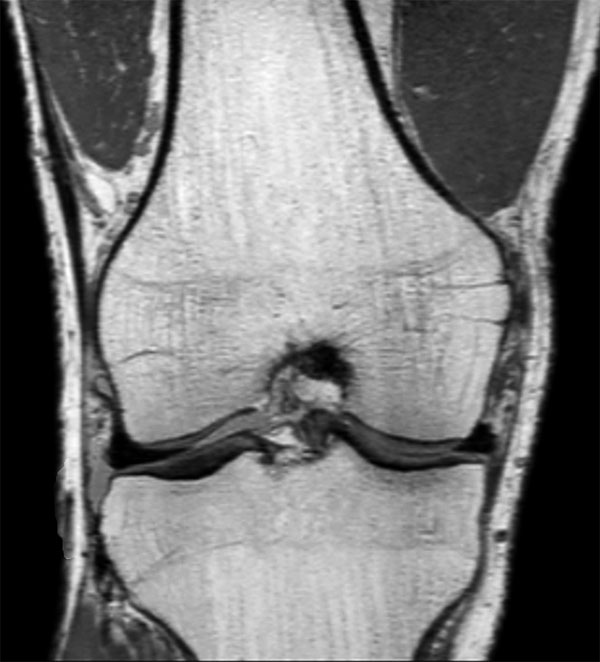

Comprehensive 3D knee imaging with MSK VIEW